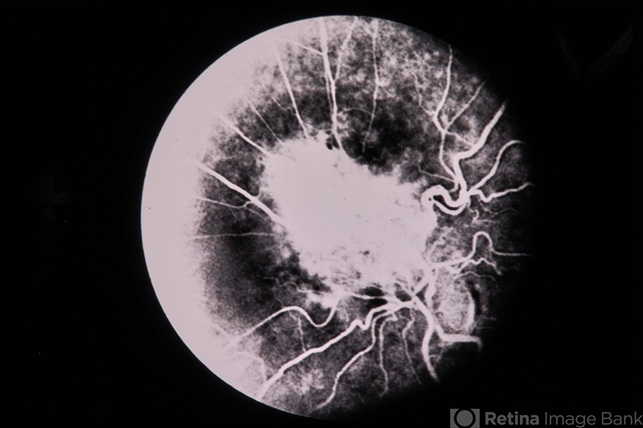

- Combined Retinal RPE Hamartoma

- combined hamartoma, retinal pigment epithelium (RPE) hamartoma

- 66-year-old white female, combined retinal & RPE hamartoma.